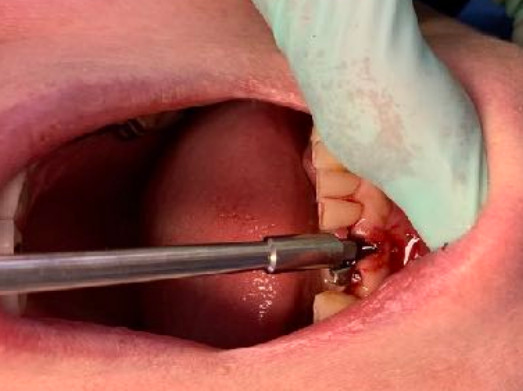

Situaz.estrattiva

postestrattivo immediato

Sequenza frese

solo lanceolata

No maschiatore

Immediato in leggera occlusione

nessuna